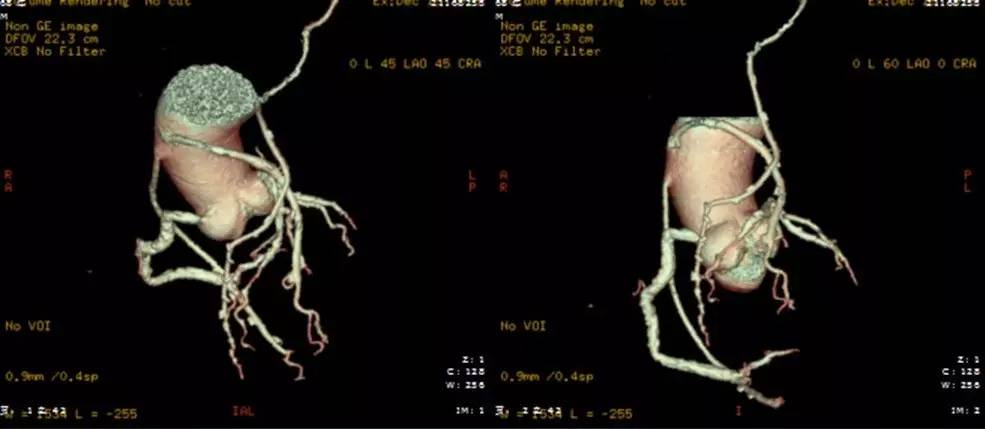

待患者病情稳定后,准备行冠状动脉造影检查。为了明确桥血管开口部位,首先行冠状动脉CT血管造影,结果显示:冠状动脉搭桥术后改变;LIMA-LAD、Aorta-D1、Aorta-RCA管腔通畅,未见明显狭窄闭塞,远端血管显示可;LCX管壁多发钙化斑块,管腔狭窄约80%~90%;左室后下壁心肌密度减低,明显增厚,多考虑陈旧性心肌梗死所致;双侧胸腔积液;主动脉粥样硬化(图3)。

图3. 冠状动脉CT血管造影